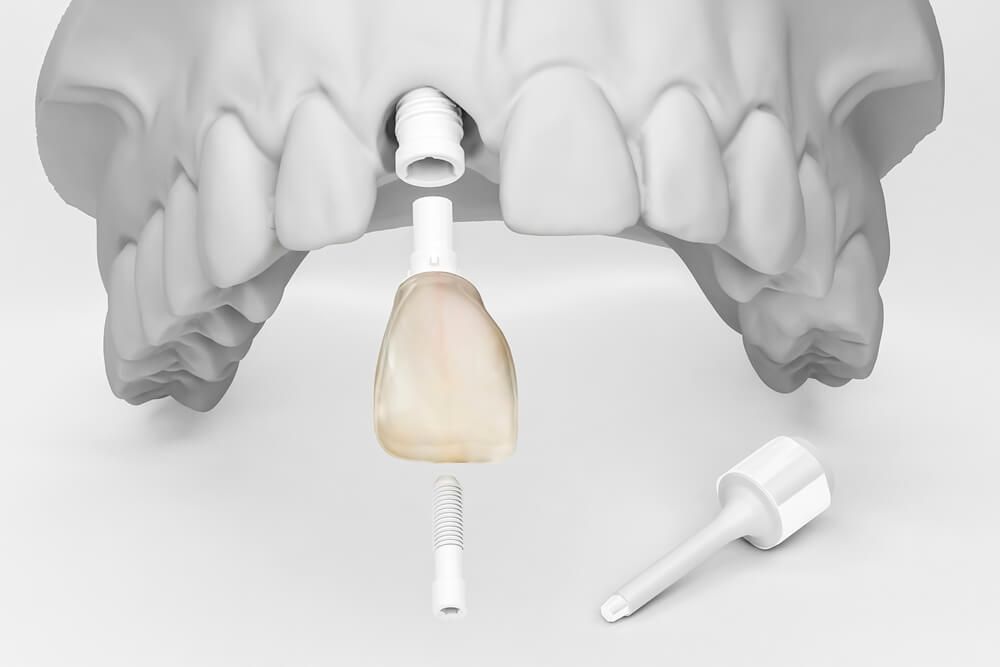

Протезирование - установка коронки на имплантат

Финальный этап восстановления зубного ряда, крепление коронковой части зуба к вросшему в костную ткань титановому основанию - имплантату.

При протезировании на имплантатах модель челюсти и конкретного зуба, и моста и всей челюсти строится в программах 3D проектирования. Они позволяют точно рассчитать высоту и ширину коронки и длину абатмента, основания соединяющего коронку с имплантом.

Коронки и абатменты изготавливаются индивидуально, по 3D модели челюсти пациента.

3D моделирование и точность фрезерного оборудования позволяет создавать конструкции которые сразу идеально устанавливаются и не меняют привычный прикус пациента, что нередко происходит при установке металлокерамических коронок изготовленных методом литья.

Соединение коронки и имплантата через индивидуальный абатмент

Важнейшая часть в протезировании на имплантатах, от которой зависит срок службы импланта. Именно на абатмент приходится вся жевательная нагрузка на протяжении всего срока службы ваших новых зубов. Он находится в самой опасной зоне подверженной скоплению бактерий и от его качеств и технологии крепления зависит надежность и долговечность конструкции. Малейшее отклонение от стандартов производителя приводит к росту зазоров и развития в них патогенной флоры или физическому повреждению имплантата.

Тип и точность соединения

Самые лучшие импланты имеют уникальное соединение с зазорами в несколько микрон. Такое соединение не допускает увеличения люфта и развития в ней бактериальной среды.